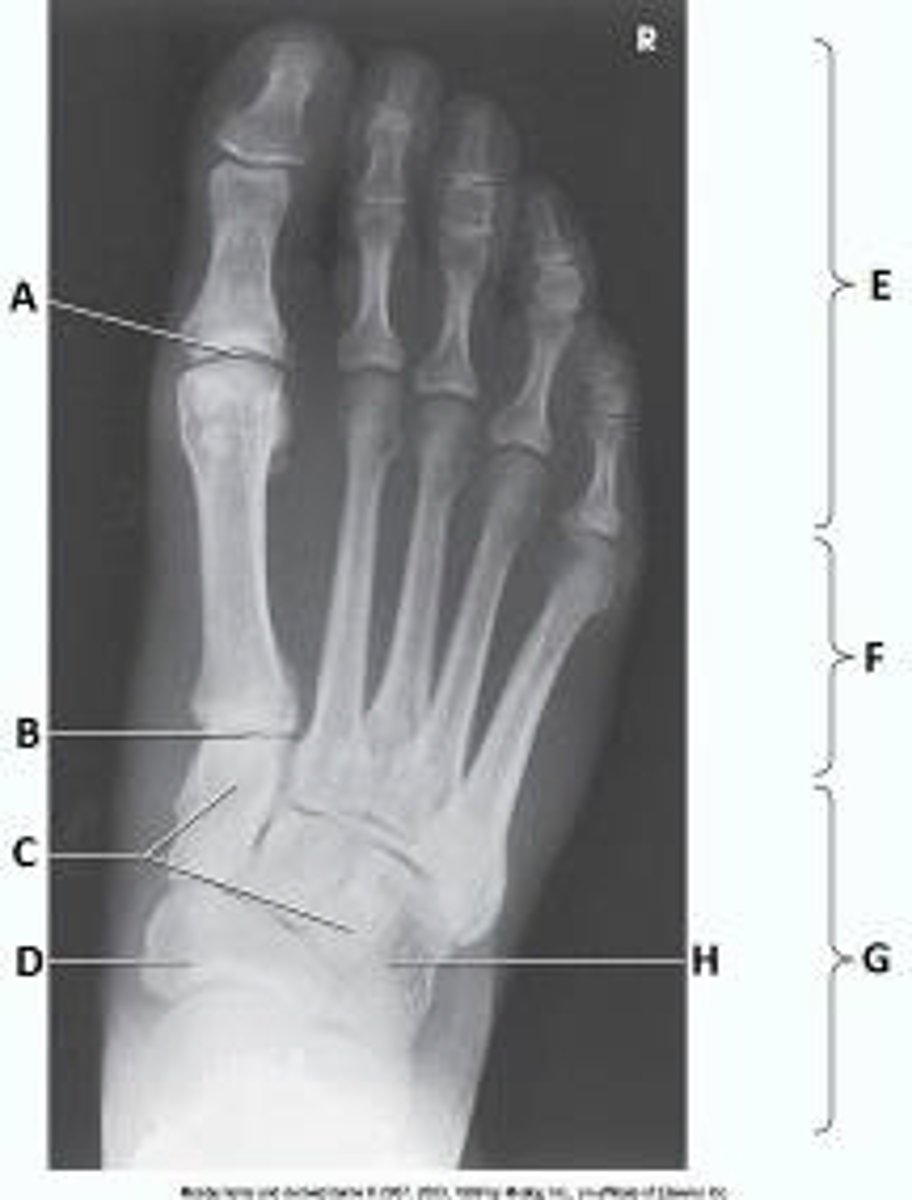

First metatarsophalangeal joint

What anatomy is labeled as letter A in the image below?

What anatomy is labeled as letter E in the image below?

Sinus tarsi

Mortise joint